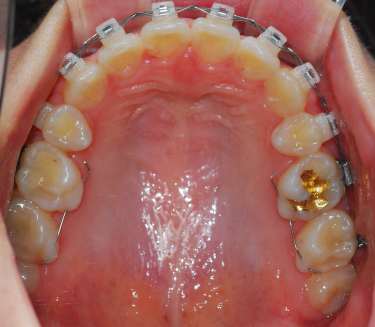

상악사진 저 위에 철사 보이시나요????? 위에 철사 역할은 위 아래 배열이 잘 맞도록 하는 역할이래요 간혹 가다 철사의 휘어진 끝부분이 돌아가서 내려오면 찔릴 수 있으니 다시 손톱으로 밀어주면 되요 2~3일정도 치아가 뻐근할 수 있다고 하네요 지금까지는 좀 뻐근하지만 그렇게 아프진 않아서 다행이에요 헤헤